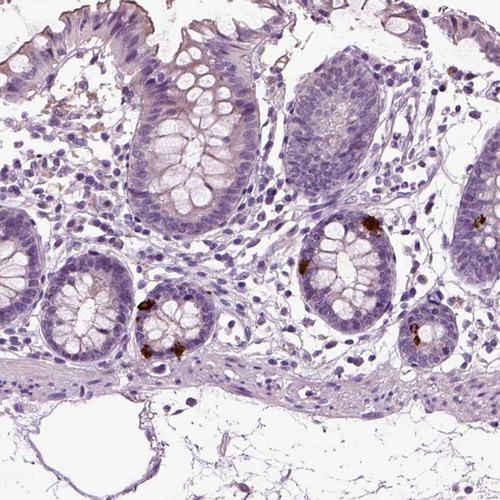

Immunohistochemistry analysis in human adrenal gland and liver tissues using HPA008759 antibody. Corresponding CHGB RNA-seq data are presented for the same tissues.